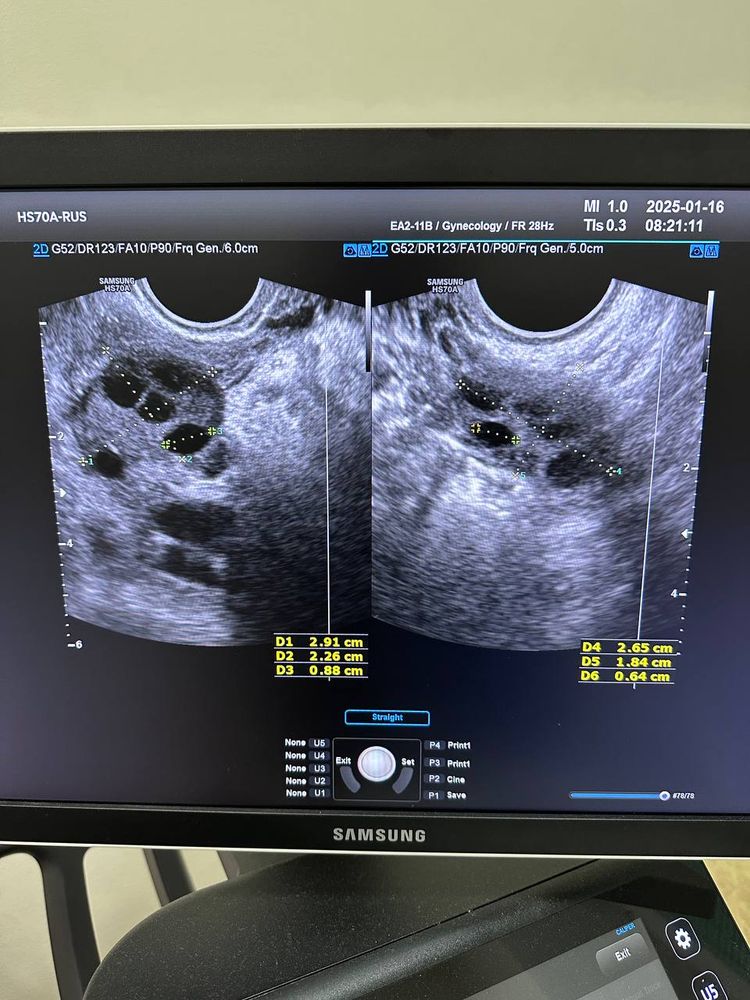

Первый раз была на узи на 7 ДЦ эндометрий 1мм, на 12 ДЦ была овуляция. На 15 ДЦ эндометрий 7,8 и нашли непонятное тело 23мм. Узист считает, что это киста, врач гинеколог считает, что это фолликул, который скоро превратится в желтое тело. Вопрос в следующем. Врач назначила принимать дюфастон с 16ДЦ 1т х2р 10 дней. Если тест будет отрицательный, то отменять, если положительный то продолжать пить. Так же свечи индомецетиловые(точно не могу прочитать из рецепта) на случай если это действительно киста. Повторной узи не назначили. Прислушаться к этим советам? как считаете? Фото прилагаю

Это первое узи, фолликулов много и максимальные до 8-9 мм